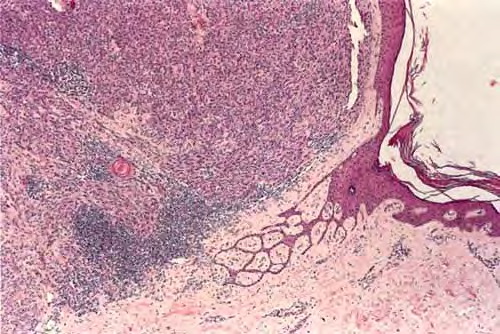

Read MoreNodular melanoma = الميلانوم العقيدي Common Tumorigenic Melanoma Including Nodular Melanoma Nodular melanoma by definition contains only tumorigenic vertical growth (sometimes associated with a precursor) and, because of this, has a poorer prognosis on the average than superficial spreading melanoma. However, when other risk factors such as thickness are controlled, the prognosis of nodular melanoma […]